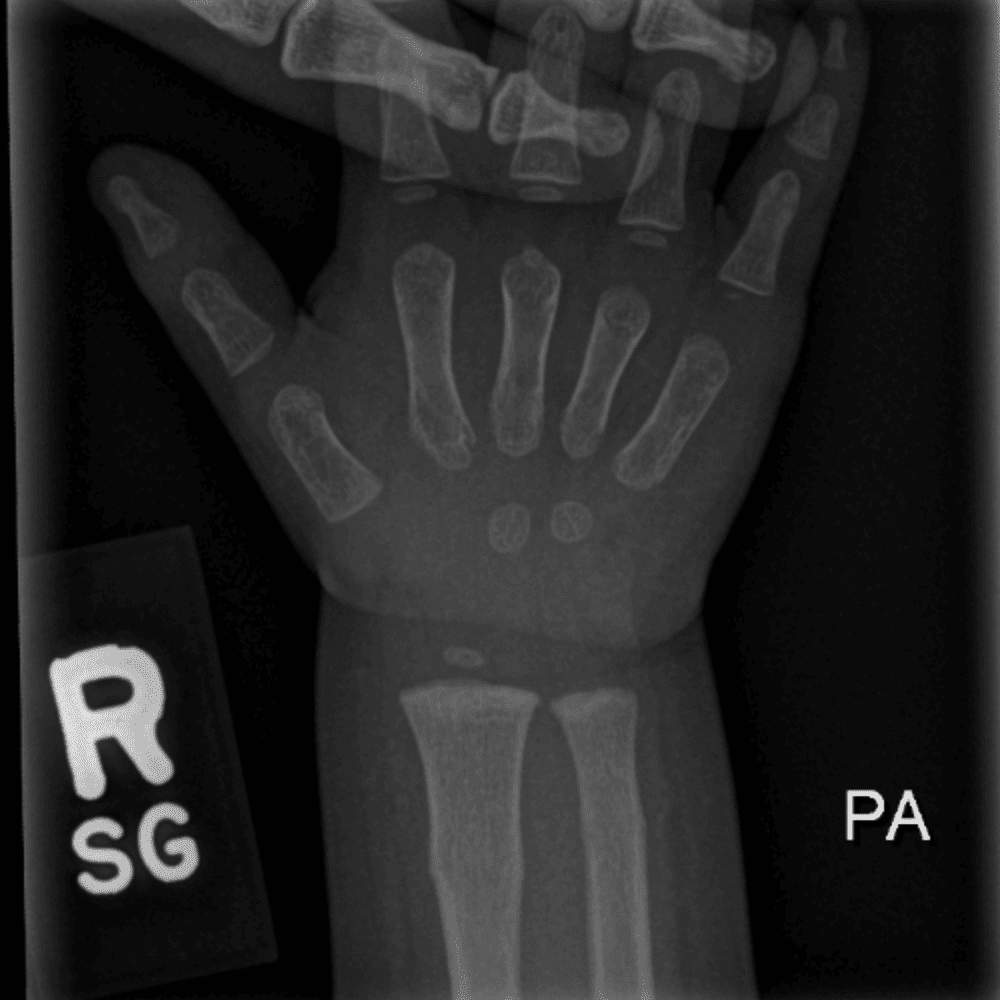

Simulates call by including subtle or difficult cases and some normals.

30 cases